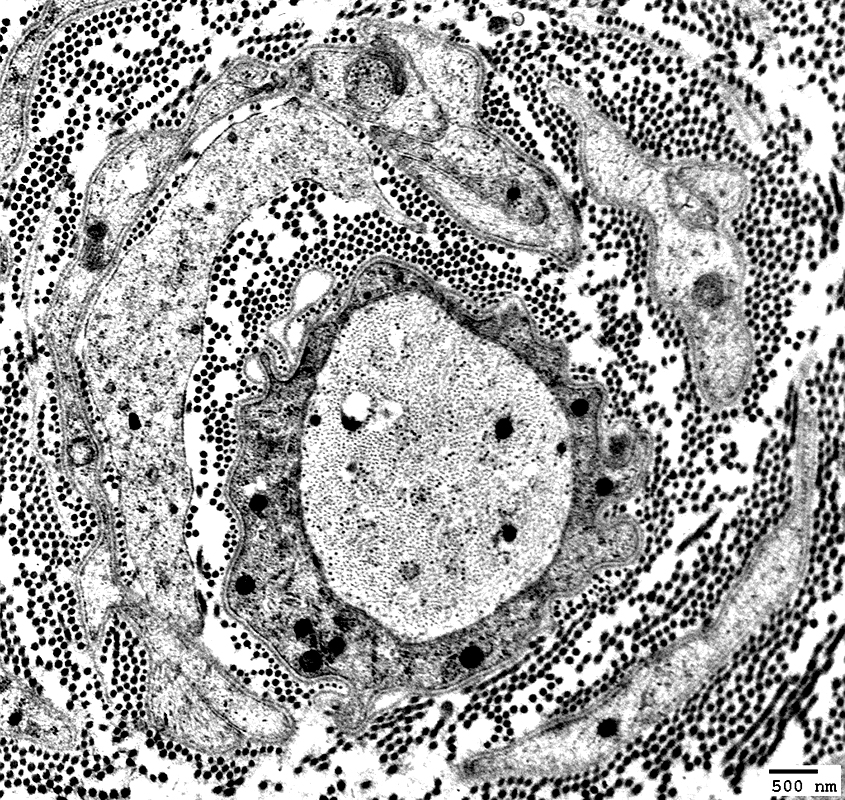

Onion Bulbs: Circumferential Layer Components

Schwann cell processes

Schwann cell basal lamina

Collagen: Between Schwann cell components

Fibroblast processes: May form outer layer

Axons in Onion Bulbs

General location: Central

Sizes: Large or Intermediate

Absent: See obsolete onion bulbs

Myelination: Varied

Normal

Thin or Abnormal

None

Electron micrograph: From Robert Schmidt MD

|